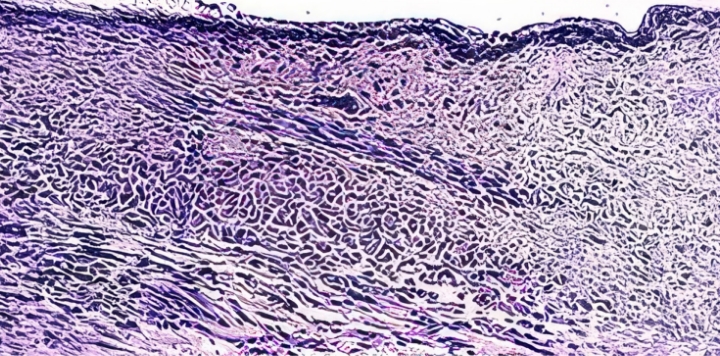

질 조직 정상 수준으로

회복되며 질 건조증 개선

질 각화세포층(분홍색)

정상군

갱년기 유도 난소 절제군

JS 트로겐 투여

질 각화세포층 및 두께 회복

JS트로겐 투여 시, 각화세포층을 포함한

질 조직이 정상에 가깝게 회복